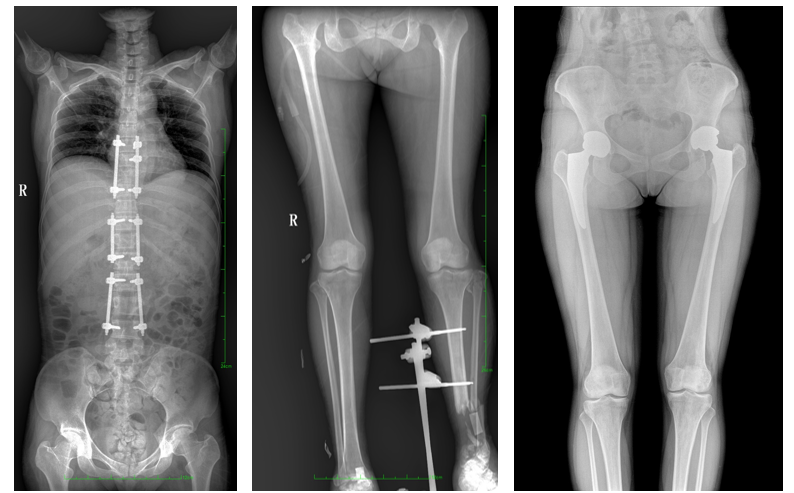

一、成像面積大。17"*34"有效視野,一次成像不拼接。相較于多張攝影再軟件拼接的DR設備,PLX8600解決了拼接圖像存在密度不均勻,拼接處圖像配準和放大效應等問題,給臨床帶來了大視野影像解決方案,可一次性覆蓋全脊柱或雙下肢影像。

PLX8600大視野平板動態DR攝影速度快,患者可以更快地完成檢查,且單次攝影輻射劑量是常規多張攝影再軟件拼接DR的1/2或1/3,低劑量給患者更多關愛。

PLX8600大視野平板動態DR可在低輻射劑量下獲得患者站立位、臥位的高質量影像。搭載自主研發的圖像均衡處理系統,能夠很好的均衡人體不同厚度組織的影像,視野大,圖像清晰,層次豐富。如果您想采購這款產品,歡迎聯系我們,咨詢電話400-025-6366。